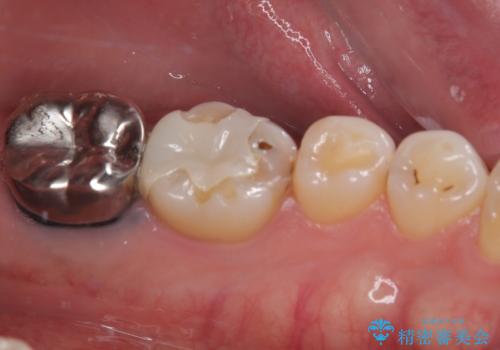

- 下顎大臼歯が噛めないほどの痛みを感じるとのことで来院された患者様です。

レントゲン写真などで診査を行ったところ、不適合な詰め物の周りから炎症が波及し、神経組織が壊死していると診断されました。

まずは根管治療を行い、症状が消退したことを確認してオールセラミッククラウンにて補綴治療を行うこととしました。